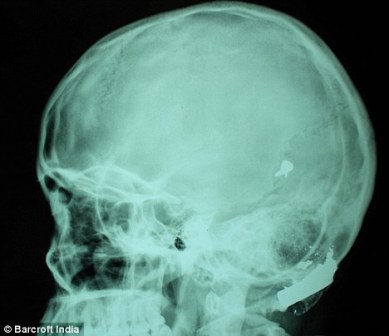

其中一顆子彈擊中她的左中耳,穿透了她的耳骨,然后擊中頭骨,嵌在了腦子里。另外兩顆子彈分別擊中她的右臂和心臟。印度Lok Nayak醫(yī)院的醫(yī)生稱,赫娜能夠康復(fù)完全是奇跡,她也足夠幸運。她的主治醫(yī)生稱:“當(dāng)我們看到她的情況時,被嚇了一跳,幸運的是她活了下來。”

這顆子彈沒有損壞大腦中控制身體機能的部分。盡管赫娜的手術(shù)很成功,但醫(yī)生表示,她還有出現(xiàn)感染和并發(fā)癥的可能。子彈毀掉了她的中耳,可能導(dǎo)致她耳聾。(楊柳)